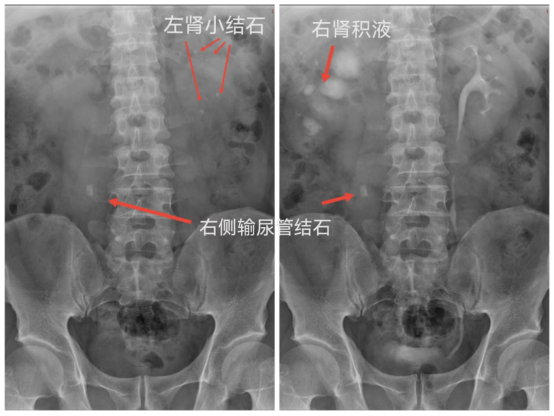

常规拍腹部仰卧位平片(KUB),准备好腹部压迫带,静脉注射造影剂,同时腹部加压,注射完后分别于7、15、30分钟摄片及解除压迫后摄片。

IMG_259IMG_260IMG_261IMG_262

静脉肾盂造影用于检查泌尿道器质性病变,可观察到尿路梗阻部位及原因。显示尿路结石造成的造影充盈缺损,对泌尿系病变有重要的诊断意义,静脉肾盂造影是放射科的常规检查项目,为进一步治疗提供可靠的指导意见及治疗方案。(供稿:放射科)